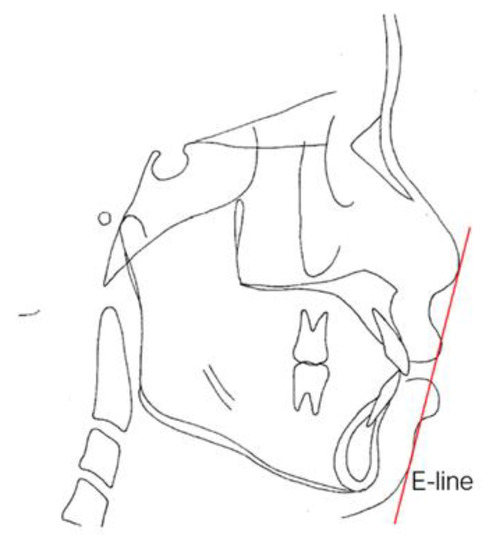

The Frankfort–mandibular plane angle (FMA) and sella-nasion (SN) to mandibular plane angle are often used to describe these three facial patterns in orthodontics (Figure 5 and Figure 6). FMAs between 27 and 34 are classified as average angles, FMAs less than 27 are classified as low angles, and FMAs larger than 34 are classified as high angles according to the data from the Taiwan Association of Orthodontists. Ricketts E line [42] (a reference line from the chin to the tip of the nose), Holdaway’s H line [43] (a line from the chin to the upper lip), Steiner’s S1 line [42] (a line from the chin to the midpoint bisecting the nasal nostril border line), Burstone’s B line [44] (a line from the chin to the subnasale), Sushner’s S2 line [45] (a line from the soft tissue nasion to soft tissue pogonion), and Merrifield’s profile line and Z angle (an angle formed by a chin-protrusive line intersecting the Frankfort horizontal plane) [37] were used to analyze the facial configurations.

E-lines and Z angles are often used for the evaluation of facial esthetics in our department of Chang Gung Memorial Hospital [37]. The lip protrusion is judged by relating it to the esthetic line (E-line). The E-line (Figure 7) is formed by joining the tip of the nose and soft tissue pogonion, which is the most protrusive point of the bony mandible. The upper lip should be tangent to the line; the lower lip should be tangent or slightly behind the E-line for Caucasians, but there is more variation from 0.2 to 4.3 mm between male and female Taiwanese. The Z angle is another angular measurement for the critical description of the esthetics of the lower face (Figure 8). This angle is formed by the Frankfort plane, and the profile line is formed by a line tangent to the soft tissue chin and to the more prominent lip. The Z angle range is typically 70–80 degrees.

Figure 7. Esthetic line (E-line). The line drawn from the tip of the nose to tip of the chin.

As shown in Table 6, the facial patterns of these 60 patients were within the average in the low margin (26.65 ± 5.53 for FMA, 35.62 ± 5.11 for SN-mandibular plane). There were no significant differences between the groups in terms of facial esthetic measurement using the Z angle, E-line to the upper lip, or the E-line to the lower lip (p > 0.05).